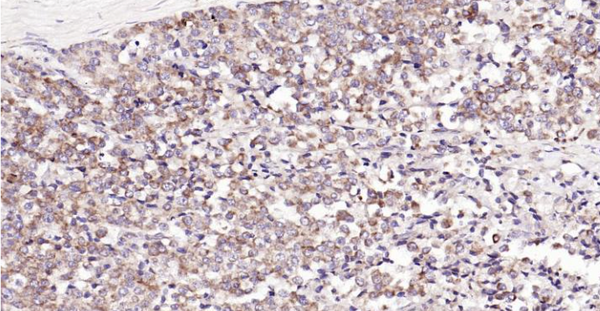

Immunohistochemical analysis of paraffin embedded human prostate tumor tissue slide using IHC0119H (Human CDKN3 IHC Kit).

The protein encoded by this gene belongs to the dual specificity protein phosphatase family. It was identified as a cyclin-dependent kinase inhibitor, and has been shown to interact with, and dephosphorylate CDK2 kinase, thus prevent the activation of CDK2 kinase. This gene was reported to be deleted, mutated, or overexpressed in several kinds of cancers. Alternatively spliced transcript variants encoding different isoforms have been found for this gene.